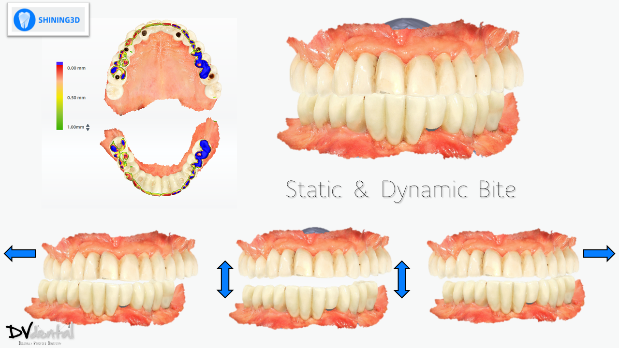

To achieve more precise occlusion, in the final step of the scanning process, Aoralscan Elite can help us capture the dynamic bite, which can be imported into the design software for subsequent dynamic occlusal design.

After the capture process is done, we send everything to the lab. The lab mounts the data on the virtual articulator with the help of the face-scan, and designs a facially driven prosthesis for the upper jaw according to the patient’s needs. The integration of the dynamic bite within the CAD software allowed us to finalize our design functionally.